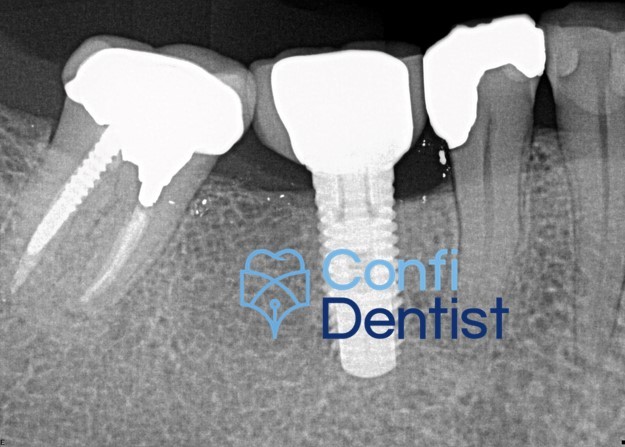

15 / 50

15. (Select ONE or MORE correct answer)

Which of the following is true regarding dental implant at site 2.6?

16 / 50

16. (Select ONE OR MORE correct answer)

There is radiographic evidence of